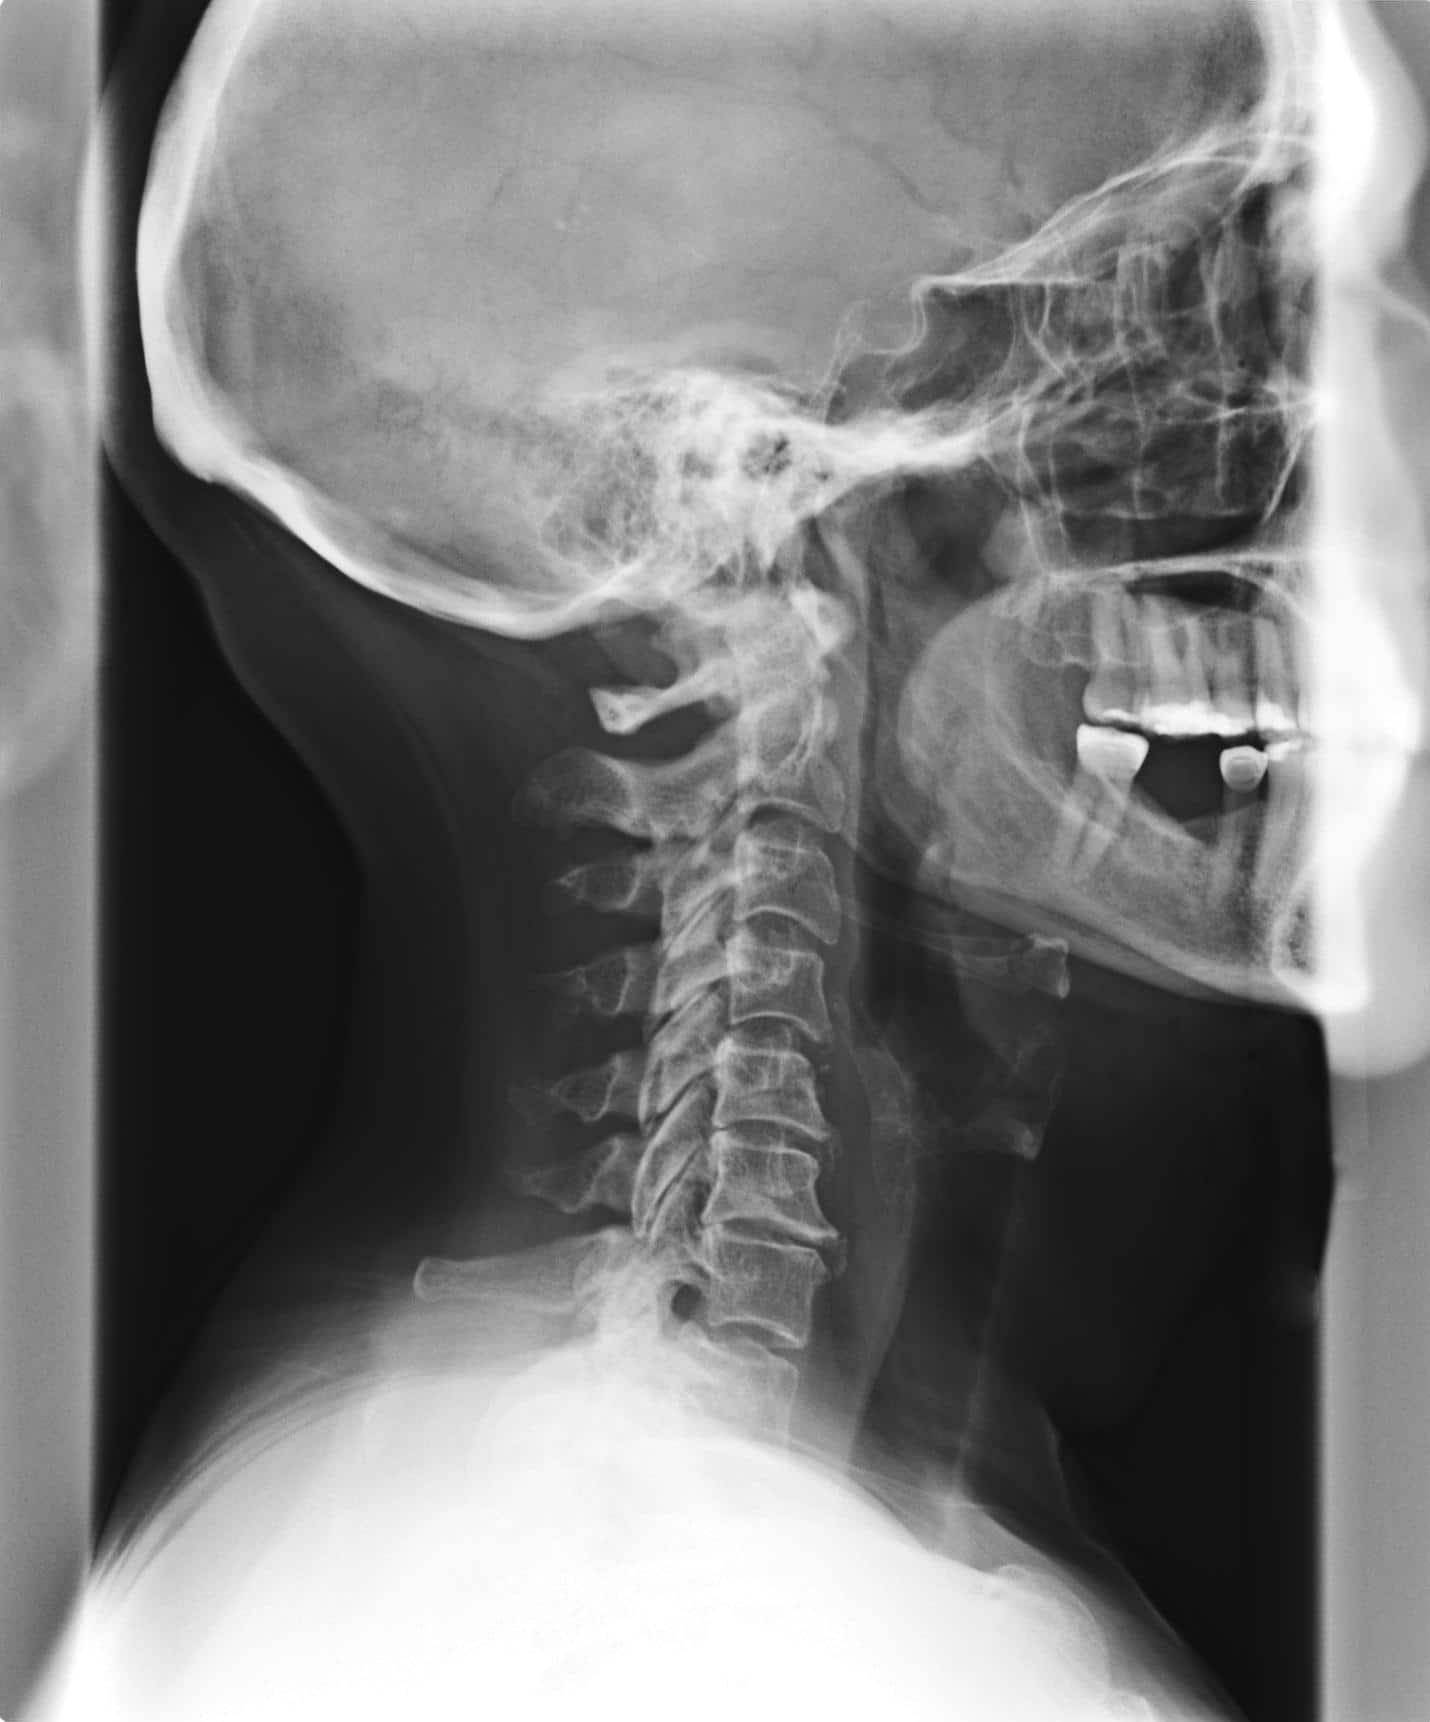

Phase III Degeneration

During the third stage, there may be permanent damage to the disc and the spine may have curvature that is abnormal. While the degeneration has worsened, chiropractic care can still make a positive impact through spinal adjustments by slowing the process down and relieving some of the issues you may be having.